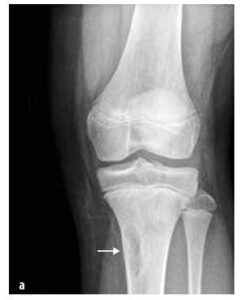

Obrázek č. 4

Klinický nález u septické artritidy

Septická artritida se vyskytuje z 50 % případů do dvou let věku a v 75 % jsou postiženy klouby dolních končetin (koleno > kyčel > hlezno) (viz obrázek č. 4). Osteomyelitida je nejčastěji lokalizovaná v metafýze.

Na infekci kosti nebo kloubu pomýšlíme u dítěte s náhlým rozvojem: horečky, nevysvětleného kulhání a/nebo abnormálního držení končetiny, odmítání používat končetinu, omezení rozsahu pohybu, muskuloskeletální bolesti ± lokální palpační bolesti kloubu či kosti a otoku se zarudnutím (viz obrázek č.4). CAVE malé děti bolest lokalizují nepřesně (např. přenesená bolest z kyčle do oblasti kolene).